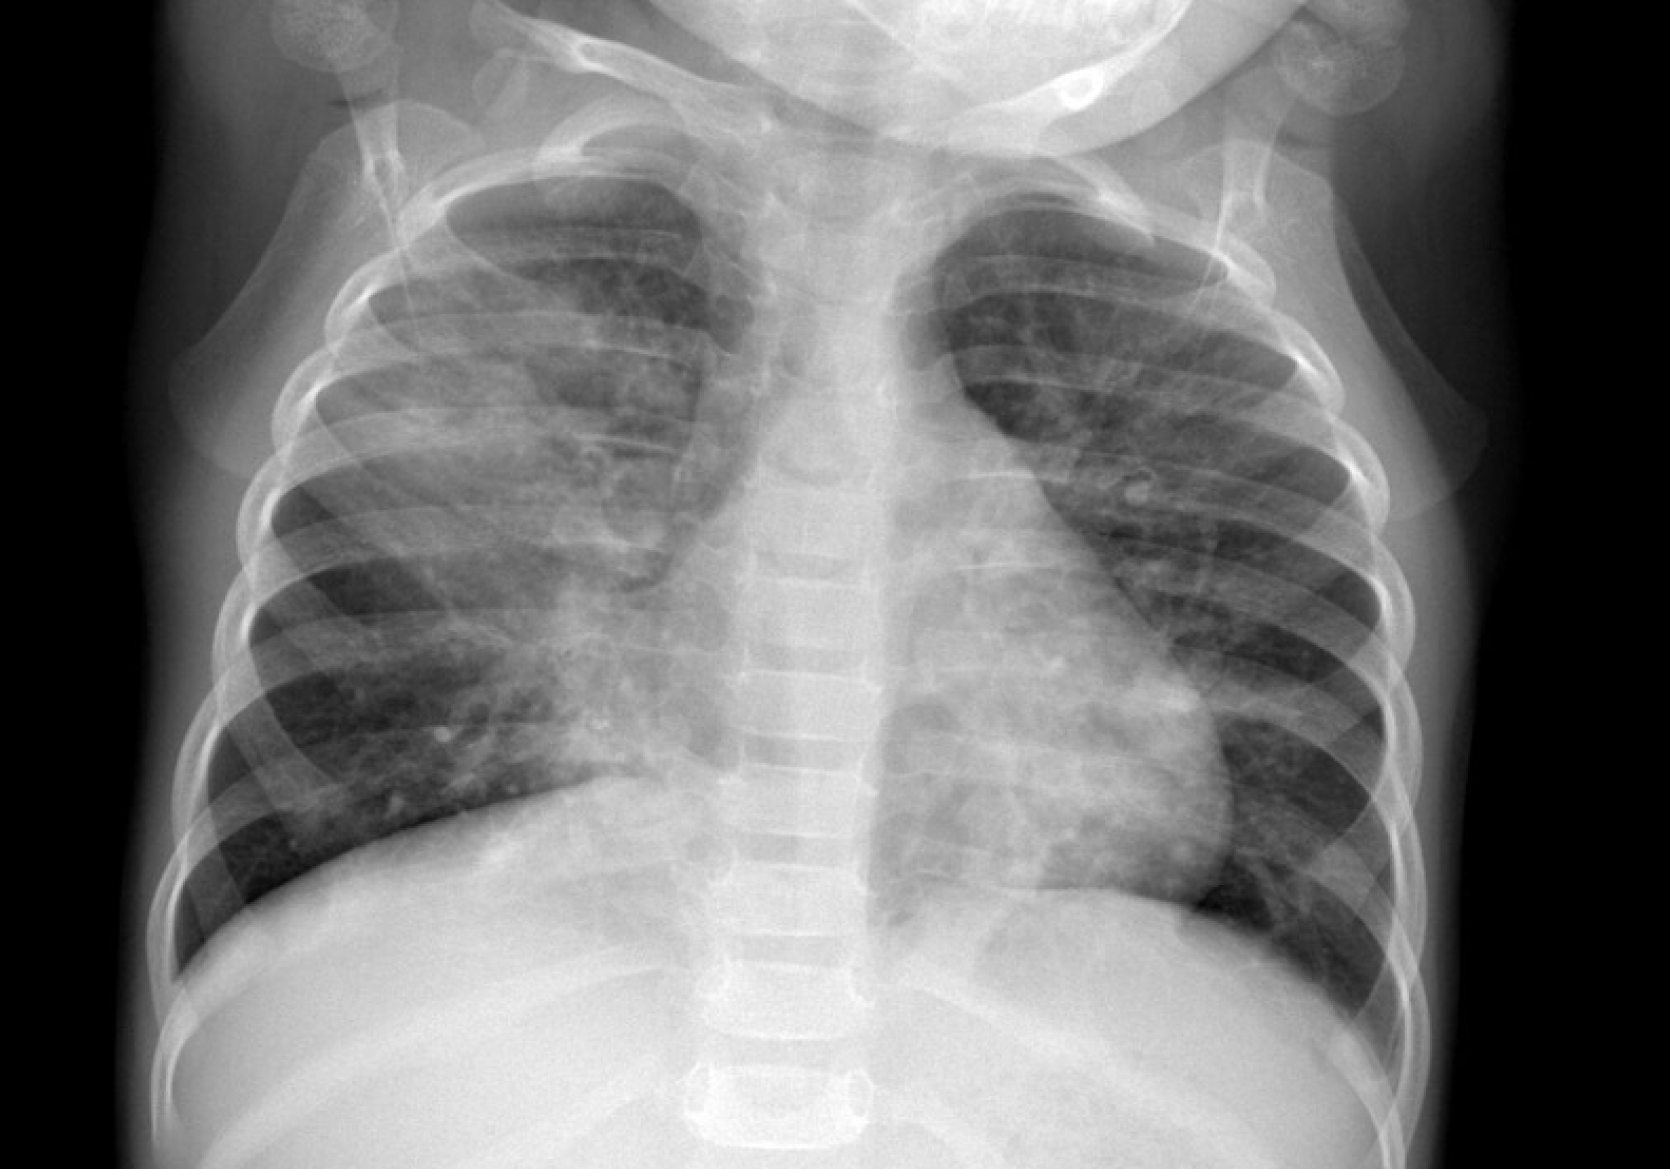

Figure 1

Chest X-ray showing right upper and middle lobe consolidation in a patient with adenoviral pneumonia who later developed post-infectious bronchiolitis obliterans.